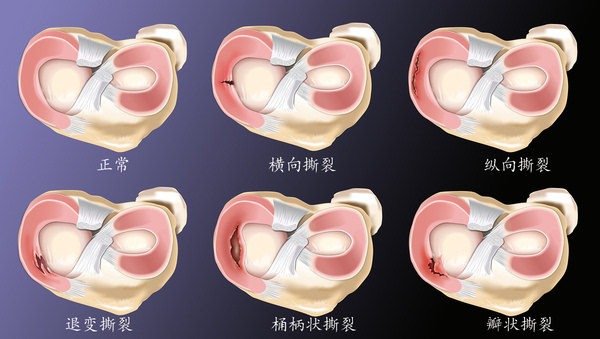

半月板损伤

341x284 - 267KB - PNG